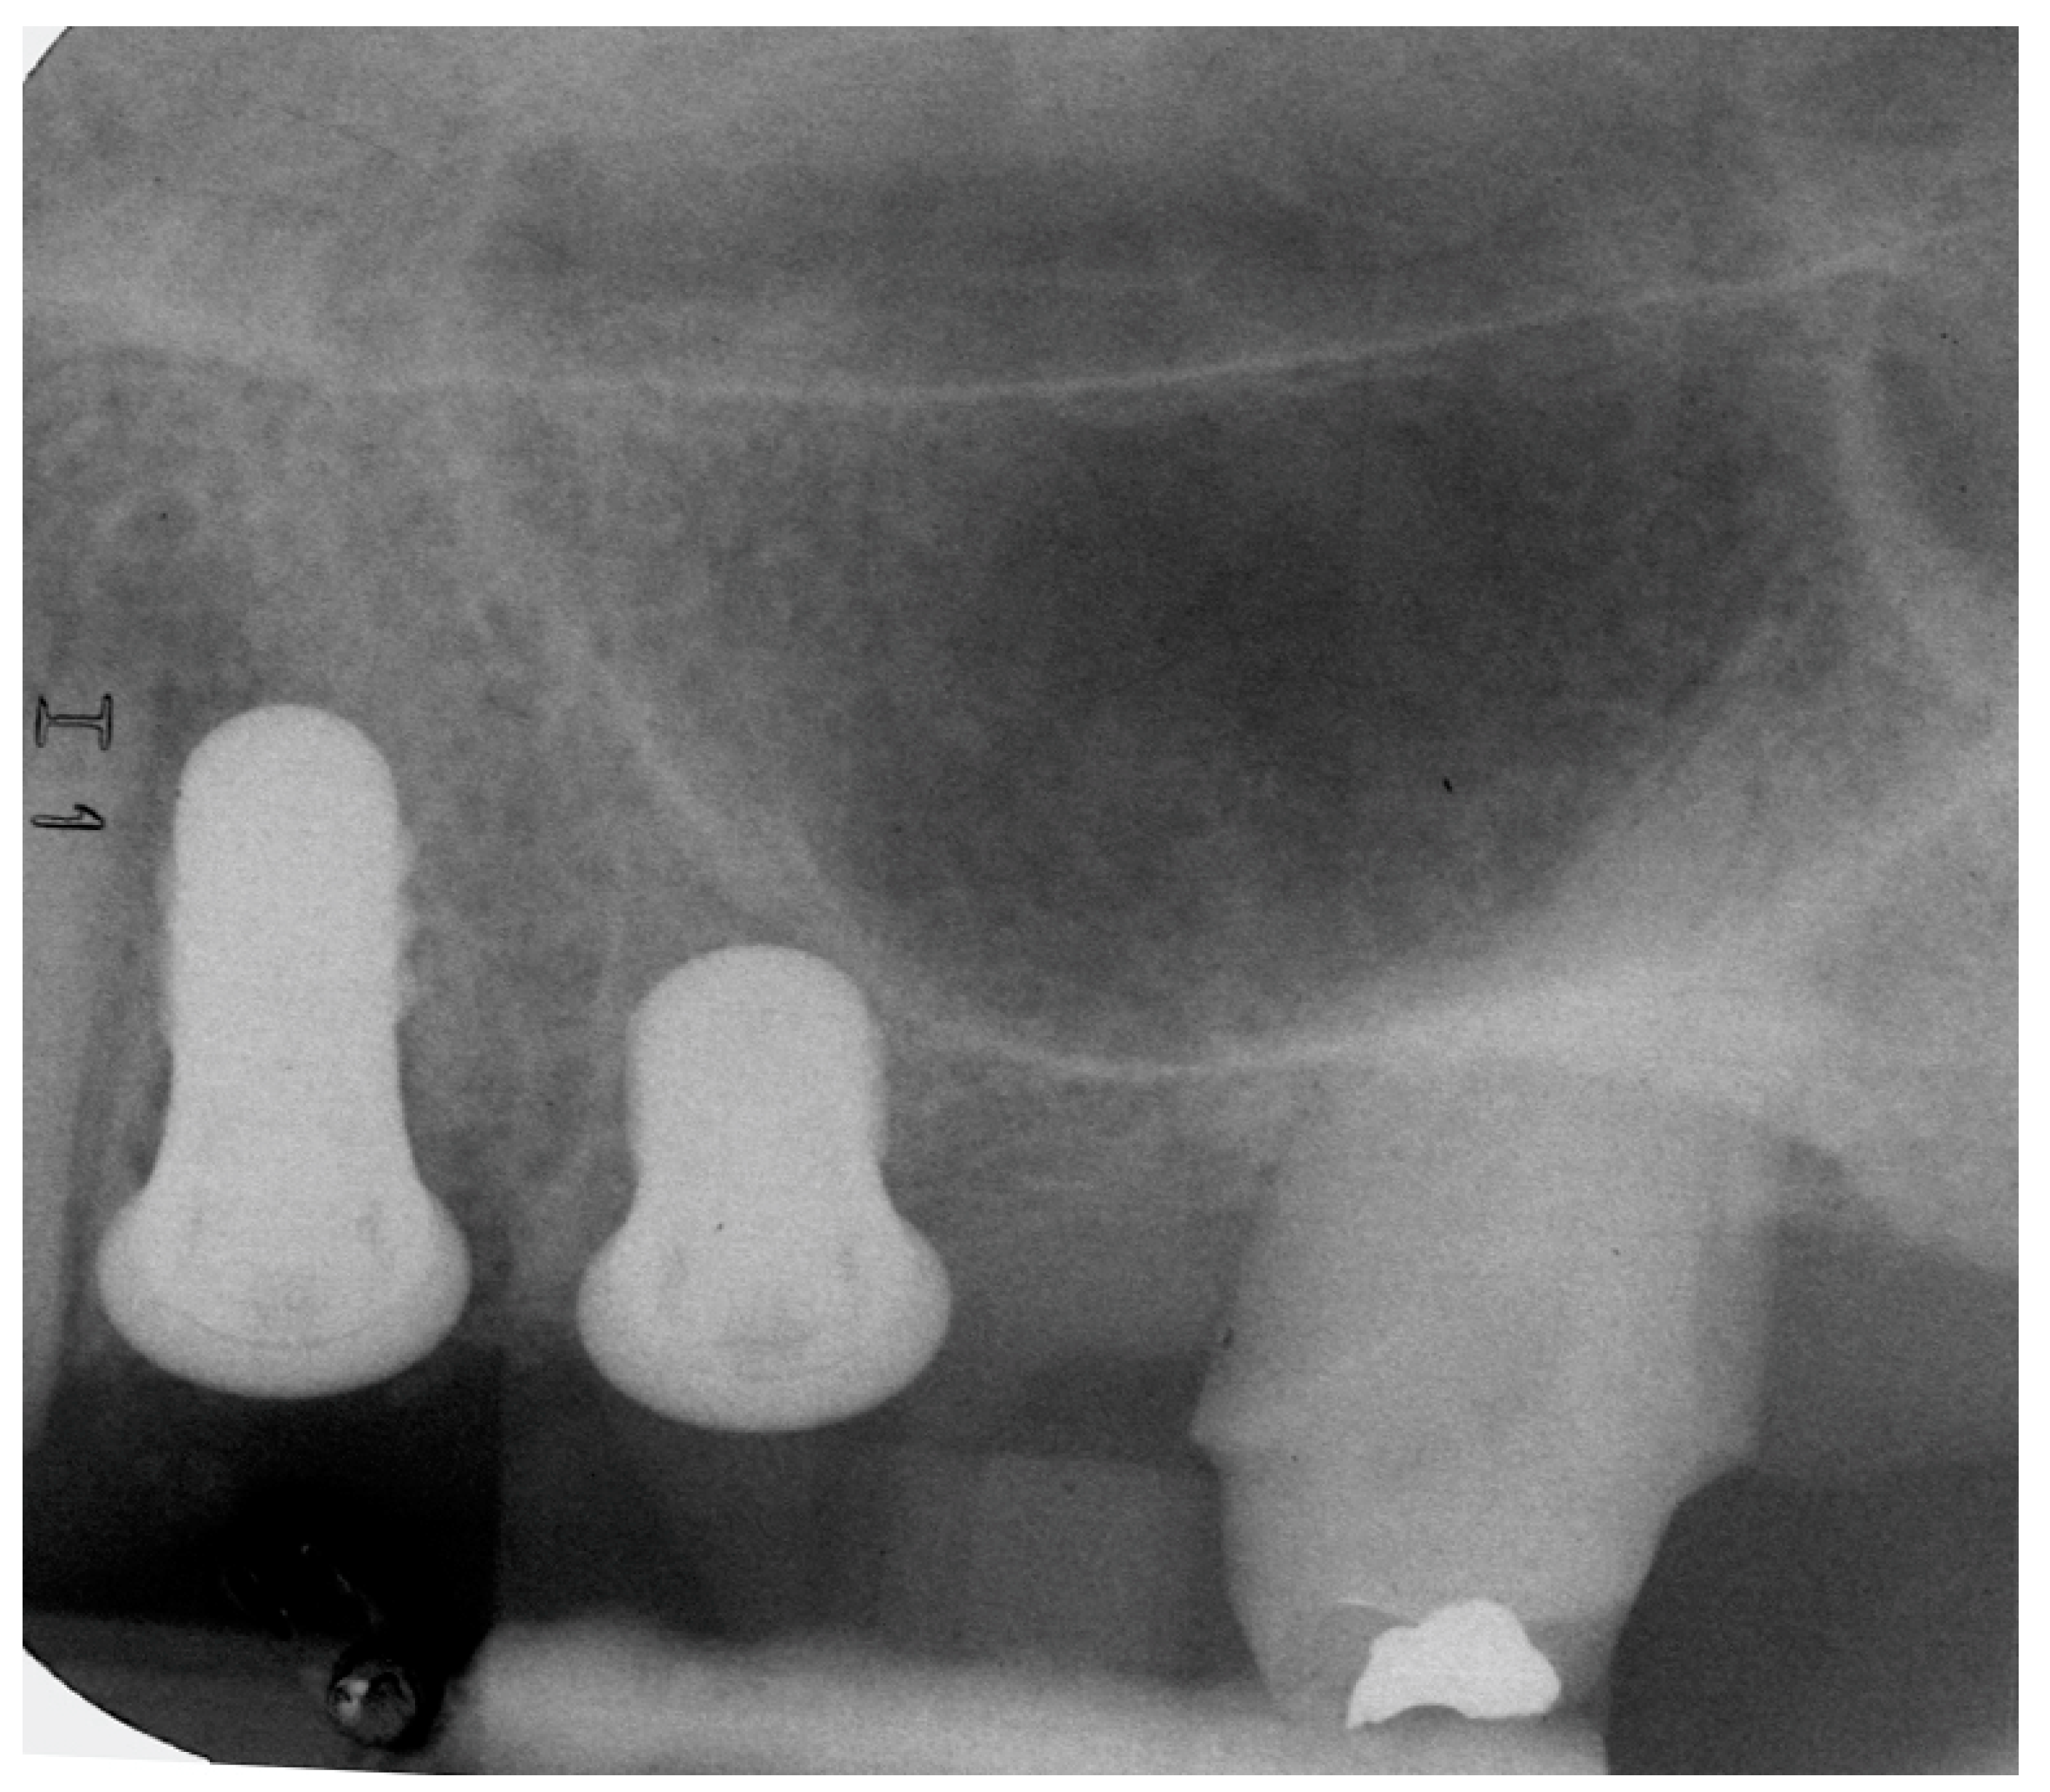

Prospective, Clinical Pilot Study with Eleven 4-Mm Extra-Short Implants Splinted to Longer Implants for Posterior Maxilla Rehabilitation

2.2. Surgical Procedure